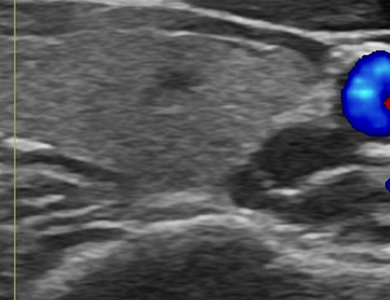

°©»ó¼±/µÎ°æºÎ(¸ñ) ÃÊÀ½ÆÄ

°©»ó¼±, ¸²ÇÁÀý, ħ»ù µî Ȥ(Á¾¾ç)ÀÌ ÀÖÀ» ¶§ ȤÀÇ Á¾·ù¸¦ ÆÄ¾ÇÇϰí,

¾ÏÀÇ ¿©ºÎ¸¦ ¹àÈ÷±â À§ÇÑ °Ë»çÀÔ´Ï´Ù.

ÁÖ»ç±â ¶Ç´Â Á¶Á÷»ý°Ë¿ë ÃÑÀ» ÀÌ¿ëÇÏ¿© °Ë»ç½Ã ÃÊÀ½ÆÄ ¿µ»óÀ» º¸¸é¼­ Àǻ簡 ½Ã¼ú¹Ù´ÃÀ» Ȥ¿¡ ³Ö°í ¼¼Æ÷ ¶Ç´Â Á¶Á÷À» äÃëÇÕ´Ï´Ù.

Çʿ信 µû¶ó ±¹¼Ò¸¶Ã븦 ½ÃÇàÇÒ ¼ö ÀÖÀ¸¸ç, ȤÀÇ °³¼ö¿Í Á¾·ù¿¡ µû¶ó ¸îÂ÷·Ê ´õ °Ë»çÇÒ ¼ö ÀÖ½À´Ï´Ù.

°©»ó¼± ÃÊÀ½ÆÄ À¯µµÇÏ ¼¼Æ÷°Ë»ç ¶Ç´Â Á¶Á÷°Ë»ç´Â °©»ó¼± °áÀýÀÌ ¾ÏÀÎÁö ¿©ºÎ¸¦ º¸´Âµ¥ ÇʼöÀûÀÎ °Ë»çÀÌÁö¸¸ ¾à 20% Á¤µµ¿¡¼­´Â Á¤È®ÇÑ Áø´ÜÀÌ ¾î·Á¿ï ¼ö ÀÖ´Ù. ÇÏÁö¸¸, °©»ó¼±¾Ï Áß ÀϺθ¦ Â÷ÁöÇÏ´Â ¿©Æ÷¼º Á¾¾çÀÇ °æ¿ì¿¡´Â ¼¼Æ÷°Ë»ç, Á¶Á÷°Ë»ç ¸¸À¸·Î Áø´ÜÀÌ ºÒ°¡´ÉÇÏ¿© ¿Ü°úÀû ÀýÁ¦°¡ ÇÊ¿äÇÒ ¼ö ÀÖ´Ù.